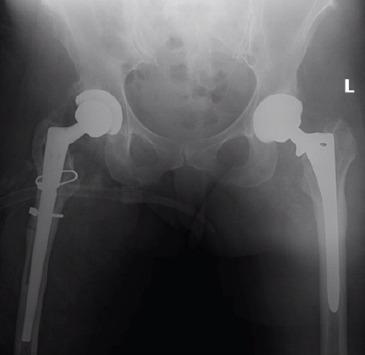

A 48-year-old female underwent bilateral staged primary THA with fully porous-coated anatomic medullary locking femoral prostheses. She subsequently sustained stem fractures of her right and left prostheses in the 13thand 14thyears after their implantation, respectively.

The bilateral nature of this rare complication in a single patient supports the notion that stem fracture results from a mismatch between the mechanical stresses encountered in vivo and the structural properties of small-diameter stems. Surgeons should be cognizant of this potential complication when evaluating patients at long-term follow-up with new-onset pain.

一名48岁女性接受了双侧分期初次全髋关节置换术,使用的是全多孔涂层解剖型髓内锁定股骨假体。随后,她在植入假体后的第13年和第14年分别发生了右侧和左侧假体的柄部骨折。

单一患者出现这种罕见并发症的双侧性支持了这样一种观点,即柄部骨折是由体内遇到的机械应力与小直径柄部的结构特性不匹配所致。在对长期随访中出现新发疼痛的患者进行评估时,外科医生应认识到这种潜在并发症。